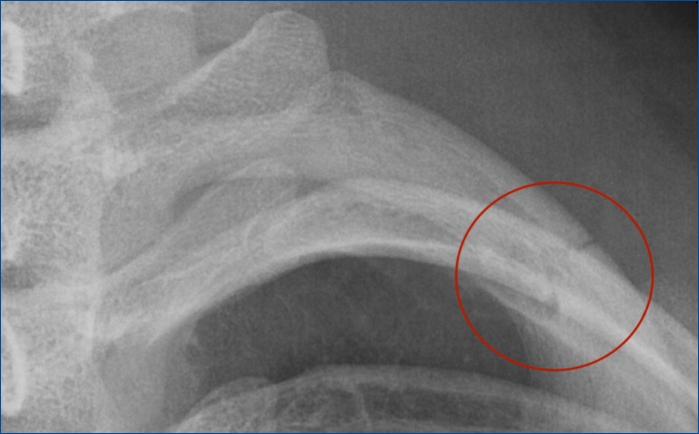

갈비뼈 피로골절 증상과 대응

갈비뼈 피로골절은 반복적인 스트레스나 충격으로 인해 갈비뼈에 발생하는 작은 균열입니다. 이러한 종류의 골절은 특히 격렬한 운동, 특정 스포츠 활동, 또는 장기간 기침이 지속되는 경우 같이 가슴 부위에 반복적인 압력이 가해질 때 발생할 수 있습니다. 갈비뼈 피로골절은 초기에는 식별하기 어려울 수 있으나, 적절한 대응을 통해 회복이 가능합니다.

갈비뼈 피로골절의 주요 증상

- 가슴 부위의 지속적인 통증: 활동 중이나 깊은 숨을 쉴 때 통증이 악화될 수 있습니다.

- 호흡 시 통증: 심호흡, 기침, 재채기 또는 웃을 때 통증이 느껴질 수 있습니다.

- 부위별 압통: 골절 부위를 가볍게 눌렀을 때 통증이 느껴지며, 이 부위는 부기와 발적을 동반할 수 있습니다.

- 호흡 곤란: 갈비뼈의 통증으로 인해 환자가 얕게 숨을 쉬게 되어, 호흡 곤란을 경험할 수 있습니다.